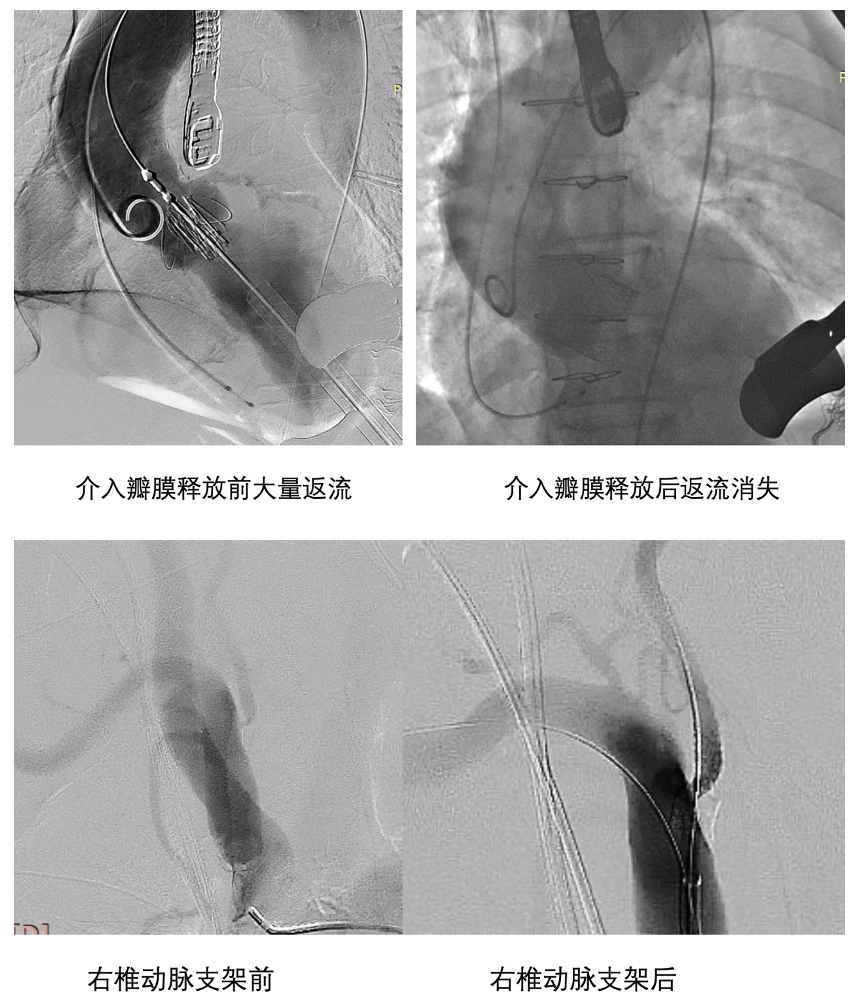

病例1:协和医院心外科与神经外科、心内科、麻醉科、手术室、重症医学科等多学科团队联合,近期完成了冠脉支架+椎动脉支架+TAVI"三联手术,凸显了杂交手术的独特价值,将经心尖TAVI与血管介入技术结合,在杂交手术室一次性解决多血管病变,实现心脑血管同步重建,避免分期手术的等待风险和重复麻醉打击,是高龄复杂患者的优化策略。